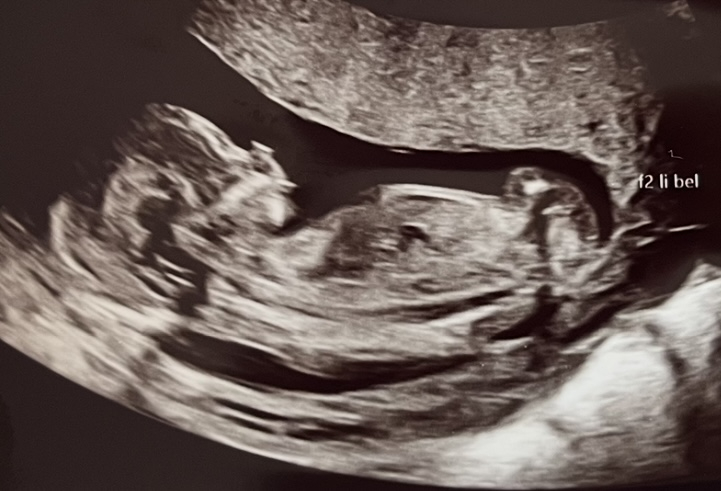

Hallo zusammen, ich war bei SSW 12+2 beim ETS. Ich habe einige Bilder erhalten. Leider bin ich sehr schlecht beim Erkennen von Ultraschallbildern. Könnt ihr mir helfen und erklären, was ich da sehe? Allen einen schönen Sonntag 🌻

War heute beim US (12+5) und bin mir nicht sicher: Ist das überhaupt der NUB und wenn ja, was würdet ihr sagen, was es wird?

Dann zeige ich auch mal mein Bild: 12SSW und die Ärztin konnte sogar schon sagen was es wird na erkennt ihr es.

Ist echt nicht schwer das Kind muss nur mitspielen 😂